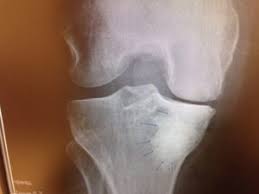

Grade 4 Subchondral Bone Marrow Edema In A Patient With Isolated And Download Scientific Diagram